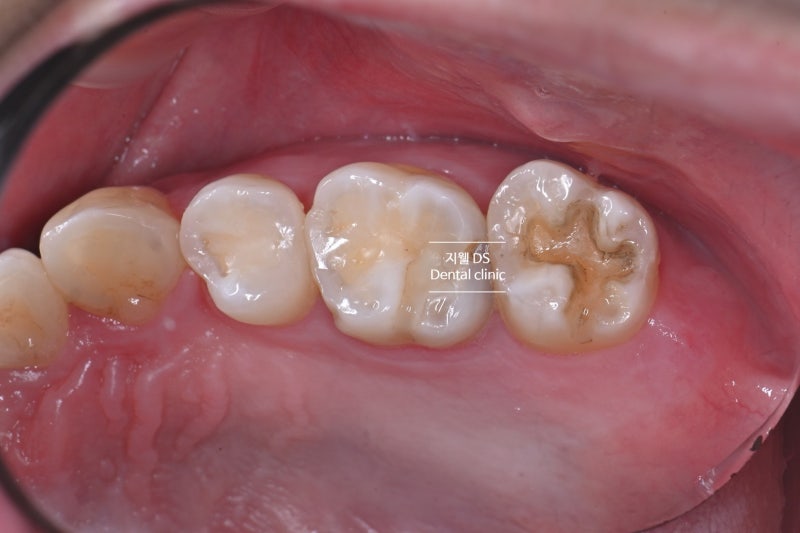

교정을 하고 구치부의 신장 관계는 나쁘지 않지만 전반적으로 협측 교두가 상당히 마모된 모습입니다.

아래턱 제2대구치부의 모든 치아에 복구 치료가 되어 있습니다. 복구된 골드 인레이 마모가 보였고 왼쪽 위턱 제2대구의 골드 인레이는 탈락했습니다.아마 비기능적인 야간 이갈이로 인해 가장 힘을 많이 받는 제2대구치 부위가 우식에 취약했을 것이고, 그로 인해 수복물이 들어갔을 것이고, 이갈이가 지속되면서 수복물이 마모되어 탈락한 것이 아닌가 의심됩니다.